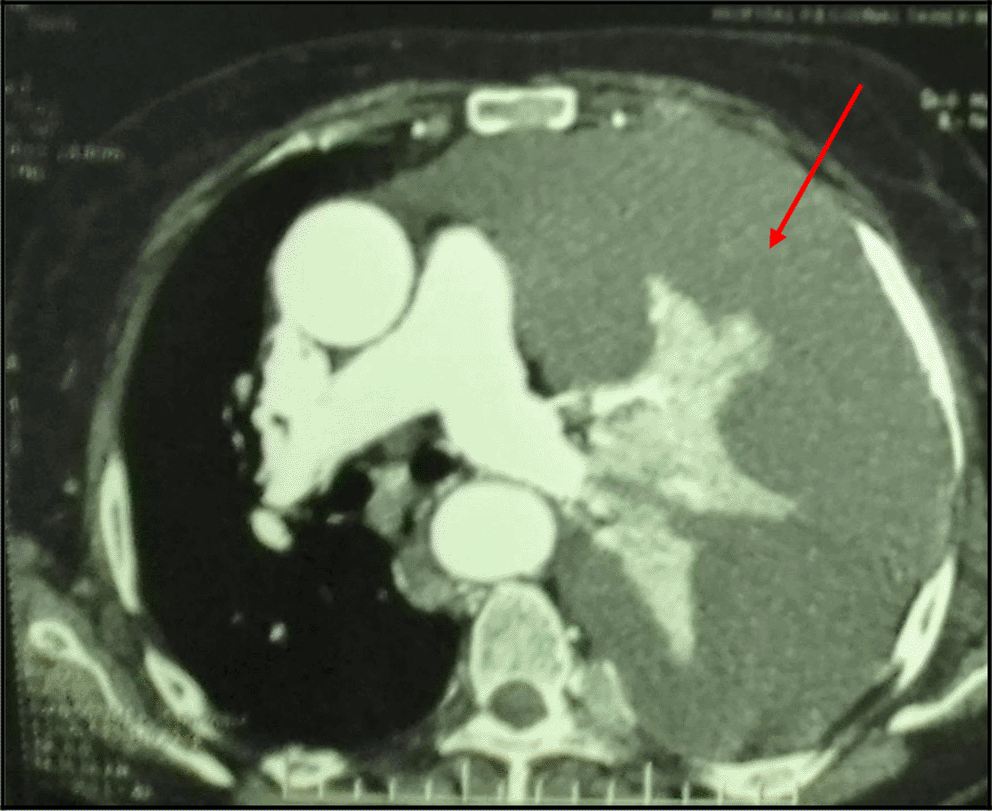

The Body-scan revealed a left-sided malignant pleural effusion associated with mediastinal adenopathy. It ruled out a pulmonary embolism. We also noticed extended secondary bone and subcutaneous lesions (Figure 3). However, it did show not any tumoral involvement of the skull or the pelvis. The echocardiography was normal.

The diagnosis was very challenging in our patient. In fact, we initially suspected an advanced stage lung carcinoma giving the chest CT scan’s findings, or a mesothelioma because of the multinodular aspect of the pleura in the chest ultrasound and “the grape-cluster” appearance as seen in thoracoscopy. The histological exam of the pleural guided biopsy helped us to assess the right diagnosis.